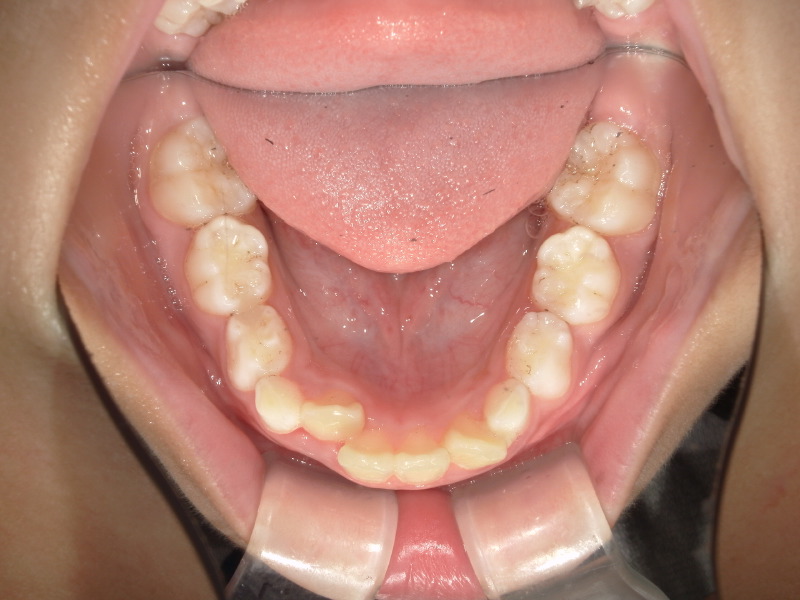

最初の検査時に撮影した写真です。

お母さんが気にされていた前歯が大きいという点ですが、歯が大きく見えるのは噛み合わせの状態や、顎の骨の成長が足りていないケースも考えられます。

下の歯が隠れており、前歯の存在が大きく感じます。

下の歯並びは2番目の歯が後ろから生えてきており、スペースが足りないようでした。